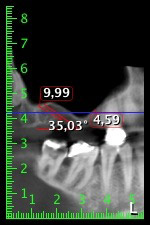

The 59-year-old patient presented with an advanced case of periodontitis, describing an unpleasant feeling and poor taste from the first quadrant in a distal direction. The clinical examination revealed generally enlarged periodontal pockets and very advanced bone atrophy in regions 16 and 14. The radiology confirmed the findings (Fig. 1). Teeth 16 and 14 could not be retained.